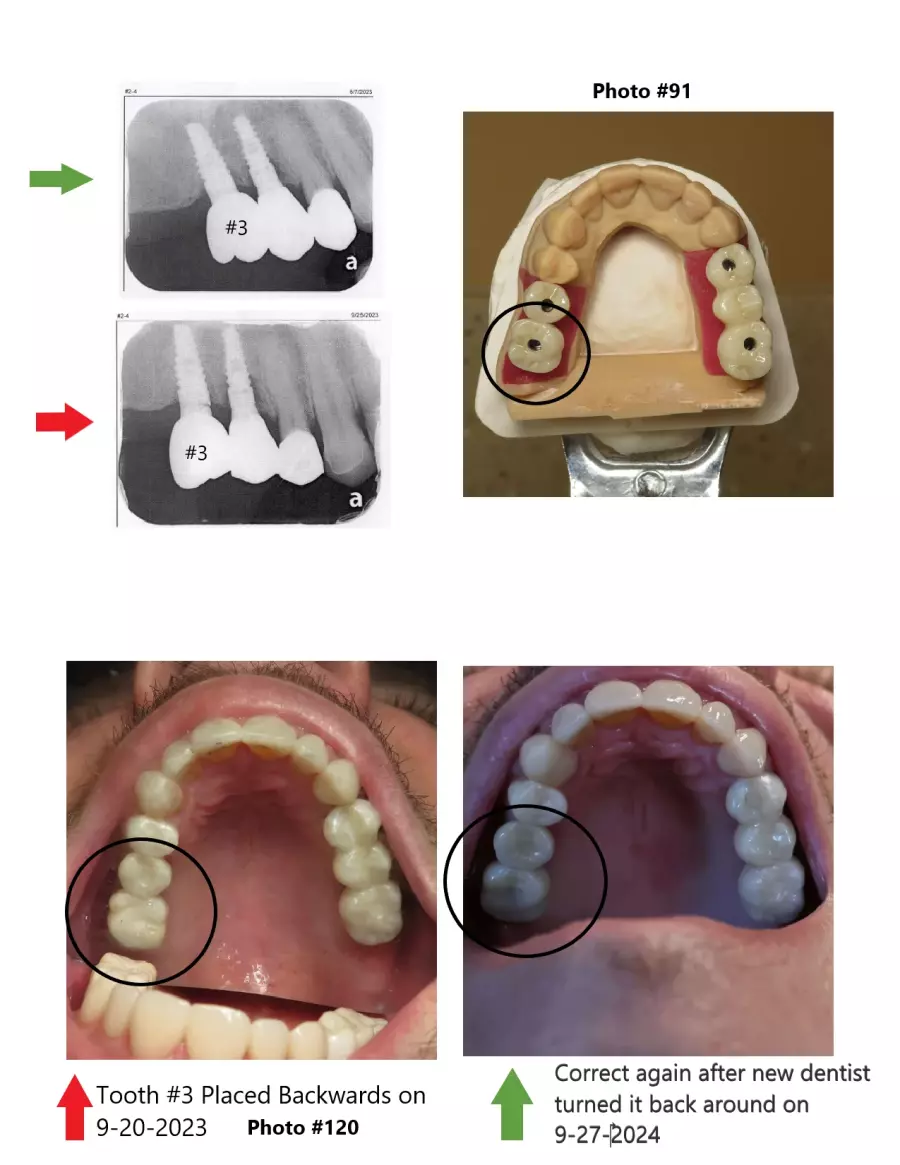

MDA Michigan Dental Association endorsed dentist Dr. Rebecca Vanderbaan & Dr. Larissa Bishop The Past President Of The WMDDS Placed A Dental Crown Tooth #3 Backwards And Wrecked My Restoration.

How did a implant supported crown get placed 180 degrees backwards then get missed then several adjustments to the adjacent teeth were made on four different separate occasions until there was no bite on 8 teeth. Permanent adjustments were made to teeth #5, #6, #7, #26, #27 and #28 all based on a crown tooth number 3 being placed backwards and then let me go with a non-functioning bite.